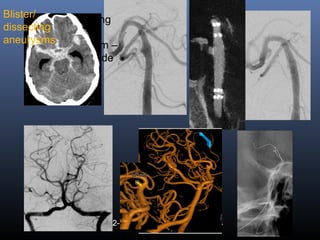

Blister aneurysms …

 Classical ICA blister aneurysms

 Dissecting aneurysm with a bleb

 Very small berry aneurysms

 Blister aneurysms (BA) are rare lesions characterized by a

hemispherical shape and fragile walls

 Non-branching sites from the dorsomedial wall of the

internal carotid artery (ICA), anterior communicating

(AComA) and basilar artery …

 Small size & atypical location- RA & 3D needed

 Blister/disecting- rapid change in size and morphology in

follow-up angiograms